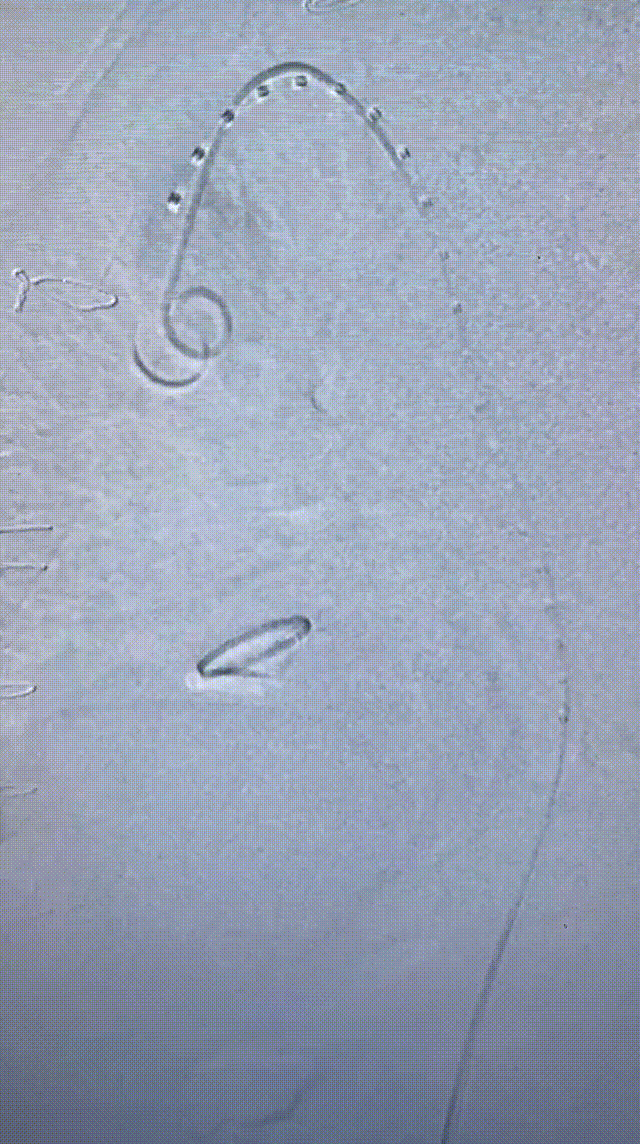

3. 交换lunderquist超硬导丝,置入DSF2265导引鞘,沿导引鞘先置入GORE® TAG® 胸主动脉覆膜支架系统 TGU313115,造影确认支架位置并释放。

gore医疗怎么样「胸有乾坤」可调可控 精准出击——四川大学华西医院肖正华教授团队:CADS治疗B型主动脉夹层病例分享_https://www.jmylbn.com_新闻资讯_第21张

释放远端CTAG

4. 继续送入近端GORE® TAG® 可主动调控胸主动脉覆膜支架TGMR313120,顶住导丝以左颈总后缘定位。

gore医疗怎么样「胸有乾坤」可调可控 精准出击——四川大学华西医院肖正华教授团队:CADS治疗B型主动脉夹层病例分享_https://www.jmylbn.com_新闻资讯_第22张

CADS支架定位

gore医疗怎么样「胸有乾坤」可调可控 精准出击——四川大学华西医院肖正华教授团队:CADS治疗B型主动脉夹层病例分享_https://www.jmylbn.com_新闻资讯_第23张

CADS释放前回撤鞘

5. CADS第一阶段释放,支架从近端向远端打开,释放至50%直径。

gore医疗怎么样「胸有乾坤」可调可控 精准出击——四川大学华西医院肖正华教授团队:CADS治疗B型主动脉夹层病例分享_https://www.jmylbn.com_新闻资讯_第24张

6. 支架近端位置微调后,再次顶住导丝,二次释放。

gore医疗怎么样「胸有乾坤」可调可控 精准出击——四川大学华西医院肖正华教授团队:CADS治疗B型主动脉夹层病例分享_https://www.jmylbn.com_新闻资讯_第25张

术中小弯侧定位造影

gore医疗怎么样「胸有乾坤」可调可控 精准出击——四川大学华西医院肖正华教授团队:CADS治疗B型主动脉夹层病例分享_https://www.jmylbn.com_新闻资讯_第26张

CADS释放一半后近端位置调整

7. CADS第二阶段释放,继续将超硬导丝顶紧大弯侧,释放CADS支架,支架由远端向近端打开至全直径,锁线钢丝全程将支架与输送系统进行固定,支架释放过程无移位,释放后,支架小弯侧贴附良好,无“鸟嘴”;最终造影可见隔绝良好,无内漏。

gore医疗怎么样「胸有乾坤」可调可控 精准出击——四川大学华西医院肖正华教授团队:CADS治疗B型主动脉夹层病例分享_https://www.jmylbn.com_新闻资讯_第27张

CADS第二阶段释放

gore医疗怎么样「胸有乾坤」可调可控 精准出击——四川大学华西医院肖正华教授团队:CADS治疗B型主动脉夹层病例分享_https://www.jmylbn.com_新闻资讯_第28张

CADS完全释放后造影